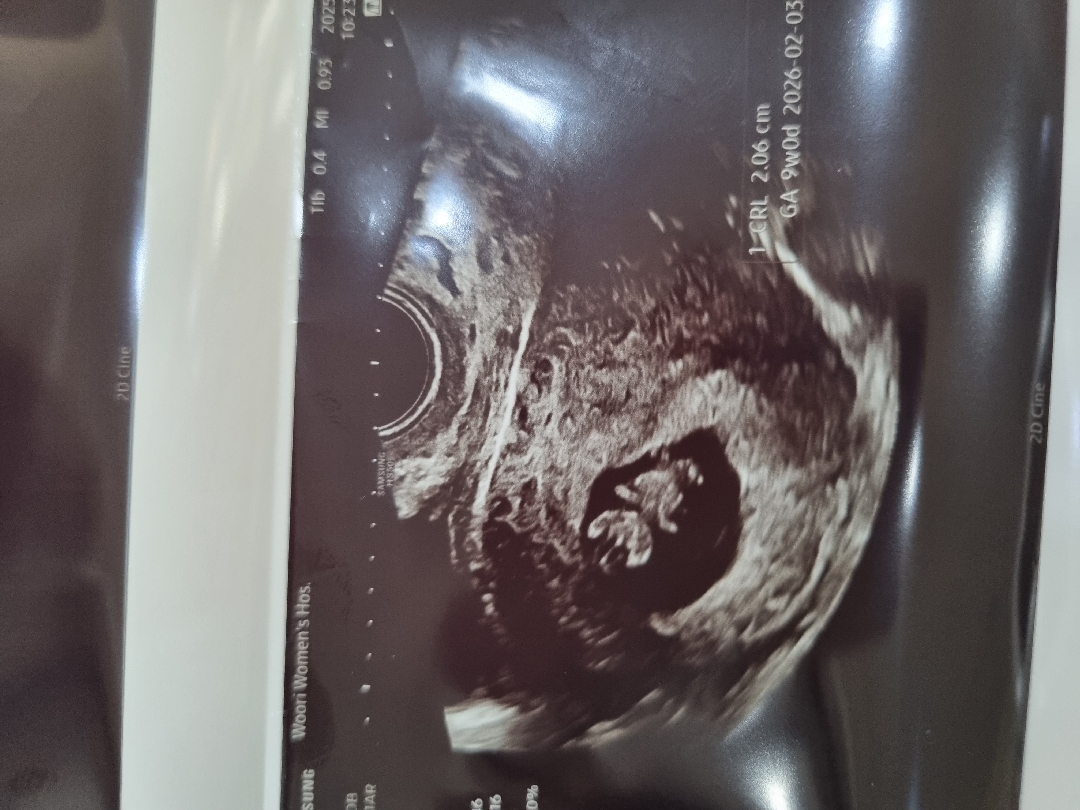

8주차 검사하러갔는데 아기가 커서 9주로 봐도될것같다고 날짜 9주로 조정하셨는데 이런건 문제없을까요ㅠㅠ

저도 8주차엔 3일을 앞서 크더니 9주에 갔을땐 하루 앞서 크고 있네요 ㅎㅎ 저랑 예정일 하루 차이나요! 🙂

저도 1-2일씩 빨라지고 있어요 9주1일차인데 2.5cm라네요